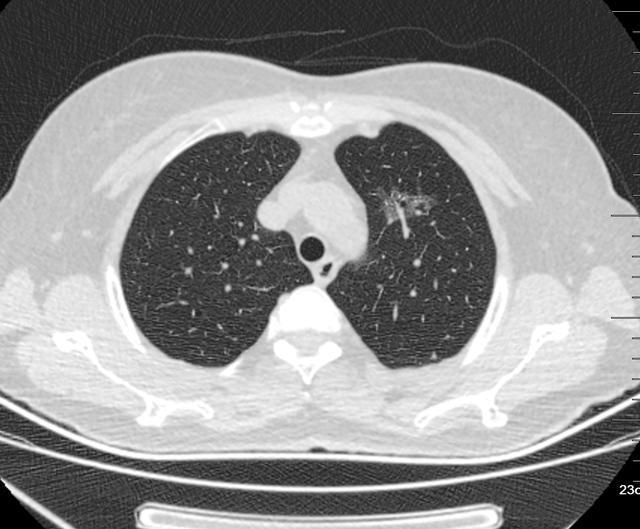

图1、2004年

图2、3 2008年1月10日

图4 2015年4月29日

图5、6 2020年5月15日

漫长的16年,一个纯磨玻璃结节从原位腺癌缓慢正常到浸润性腺癌早期阶段(影像估测),所以说纯磨玻璃结节是不可怕的,可以安心随访,到合适的时机手术完全来得及,不要上来动不动就手术,动不动就消融!